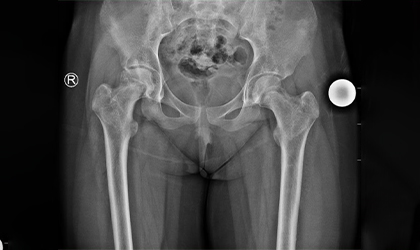

Bilateral Knee Replacement Case Study

Independent, Pain-Free, Walking

This 68 year old lady has a condition called protrusio where the socket becomes weak and protrudes into the pelvis